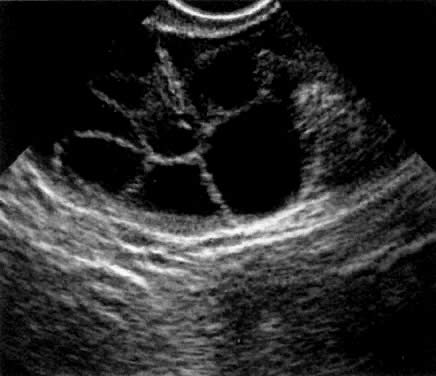

In the late 1980s, vaginal probe real-time sonography became available, with improved gray scale images and better resolution. Transvaginal oocyte aspiration was less invasive and more efficient than laparoscopic oocyte aspiration (Fig. 2). Therefore, the GIFT technique was modified again. Vaginal aspiration of oocytes was followed by laparoscopy, tubal cannulation, and sperm and oocyte deposition into the ampulla. Minilaparotomy for GIFT was almost completely abandoned in the late 1980s. The superiority of laparoscopy was recognized by most GIFT programs, and this technique became the standard approach to GIFT.8

Fig. 2. A transvaginal sonographic image of an ovary stimulated by human menopausal gonadotropins. An aspiration needle (echogenic white line) is used to aspirate the follicles.